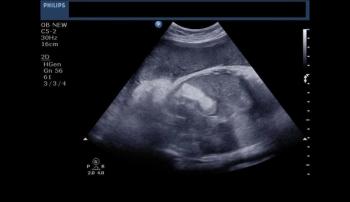

This patient was a young woman with non specific pelvic and perineal pain. What would you diagnose on the basis of these images of the uterus?

Two of the images are in 3D. Besides the 10 weeks pregnancy, what else do you find?